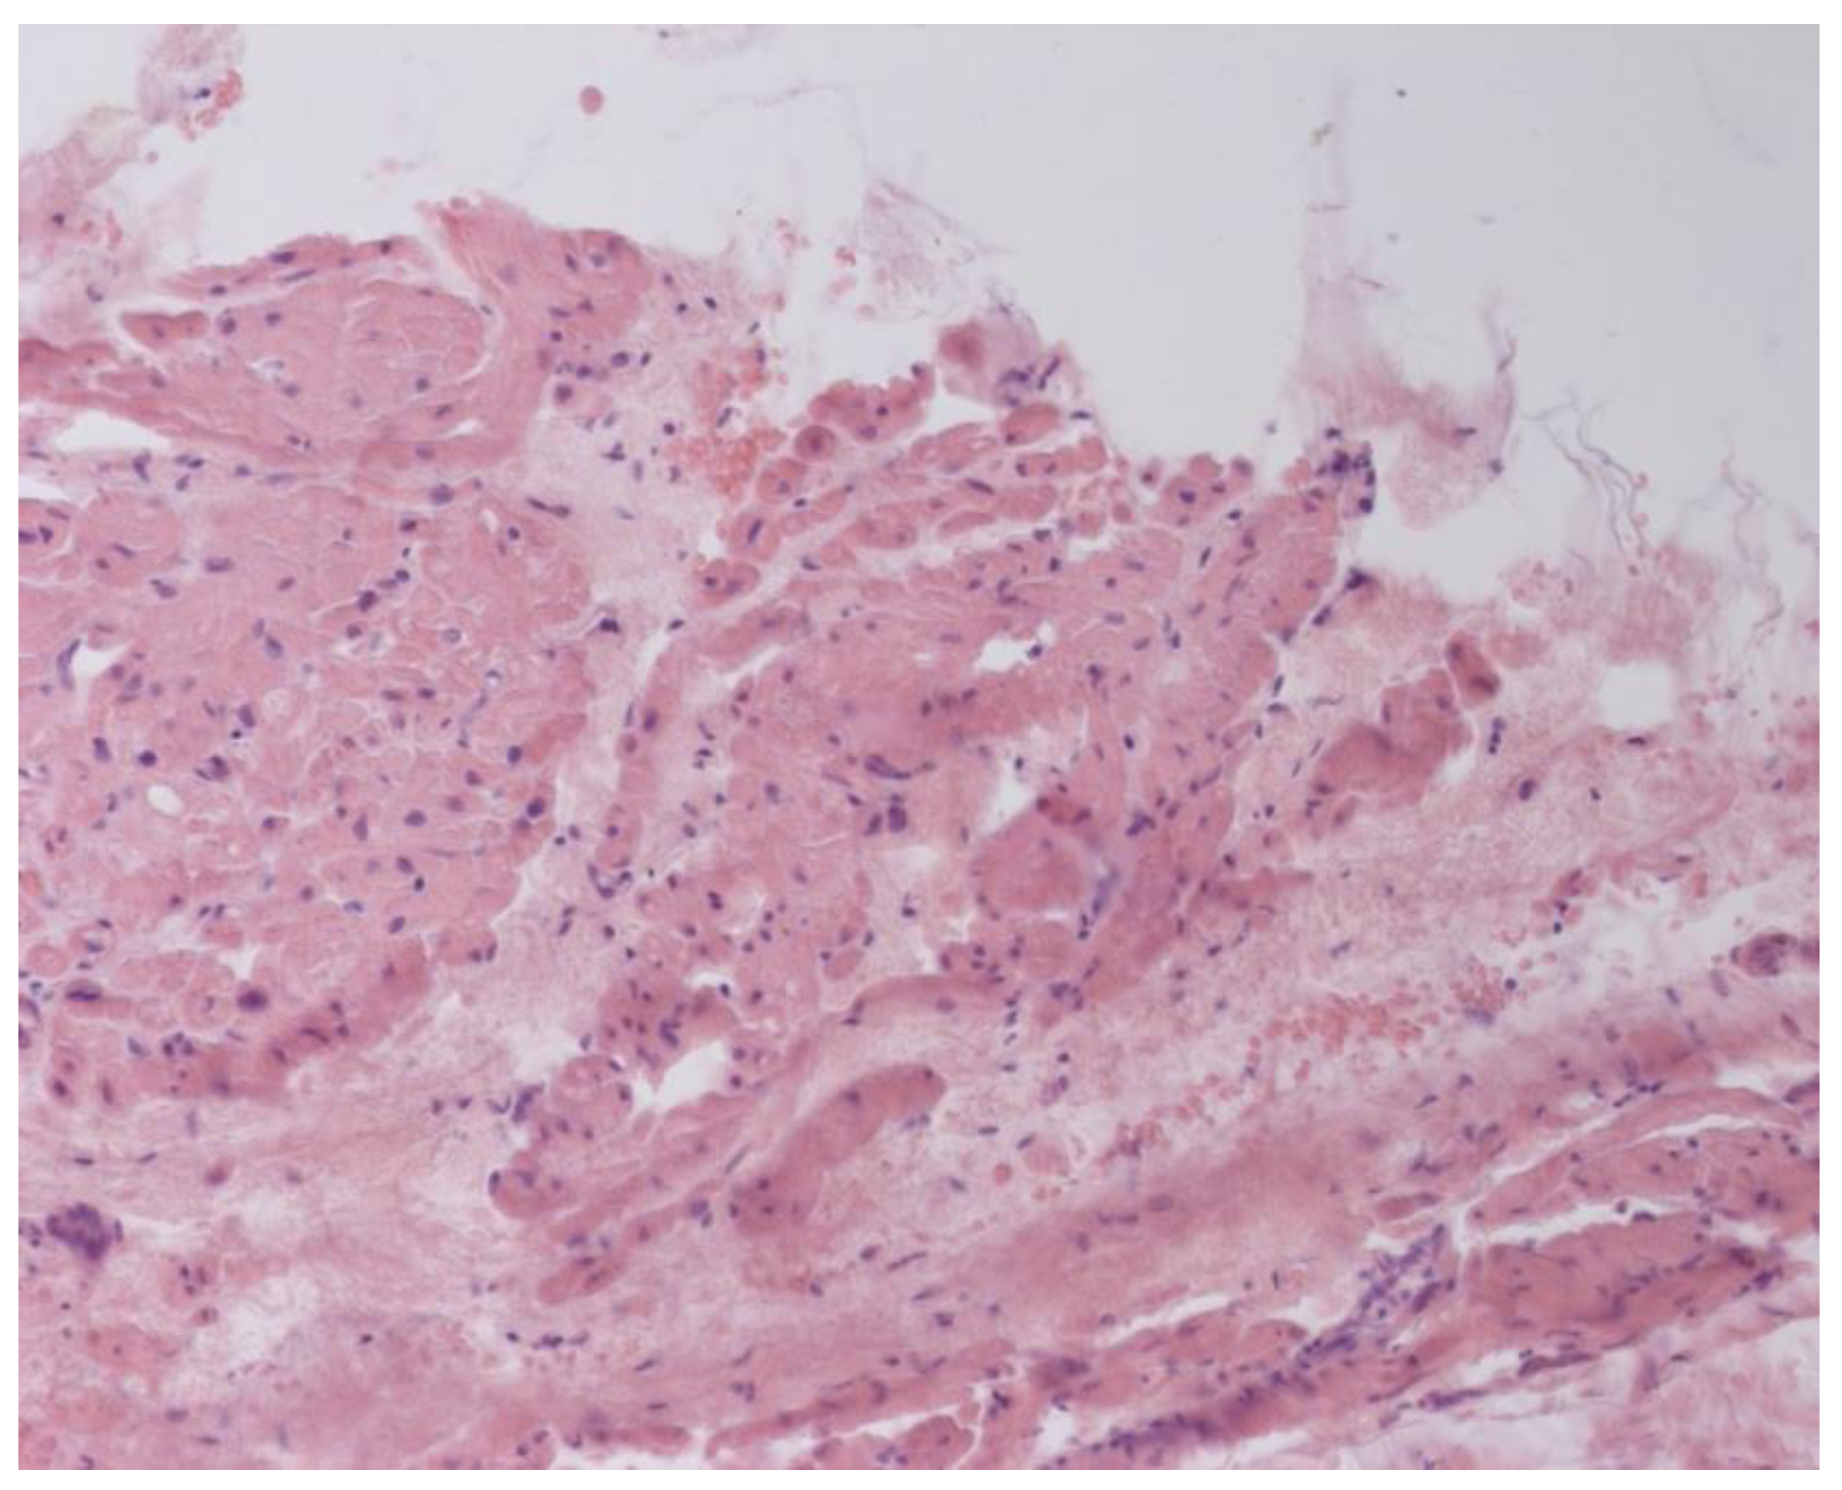

Inflammatory changes in the myocardium were detected in 32 patients (47.8%), including nine patients (28.1%) with lymphocytic infiltration of less than 14 lymphocytes per mm2 (Figure 4 and Figure 5). The data obtained with EMB from RV and IAS were comparable. Inflammatory changes in RV correspond to a similar finding in IAS, while fibrotic changes in RV correspond to the same evidence in IAS. According to the results of immunohistochemical analysis, the virus expression was detected in one of these patients (3.1%). A combination of human herpes simplex virus type 2 and Epstein-Barr was found. No virus expression was detected in the remaining patients.

Figure 5. Endomyocardial infiltration of IAS with lymphocytes, ×200. Hematoxylin-Eosin Staining.

Jcm 12 01254 g005